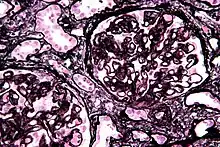

| Micrograph of diffuse proliferative lupus nephritis showing increased mesangial matrix and mesangial hypercellularity. Kidney biopsy. PAS stain. | |

Class IV disease (Diffuse proliferative nephritis) is both the most severe, and the most common subtype. Class VI (advanced sclerosing lupus nephritis) is a final class which is included by most practitioners. It is thought to be due to the chronic interferon exposure.[11]

| Class IV | Diffuse proliferative nephritis | 40% | More than 50% of glomeruli are involved. Lesions can be segmental or global, and active or chronic, with endocapillary or extracapillary proliferative lesions. | Under electron microscopy, subendothelial deposits are noted, and some mesangial changes may be present. | Clinically, haematuria and proteinuria are present, frequently with nephrotic syndrome, hypertension, hypocomplementemia, elevated anti-dsDNA titres and elevated serum creatinine.[13] Kidney failure is common.[12]![]() Diffuse proliferative lupus nephritis as seen in a pathology specimen |